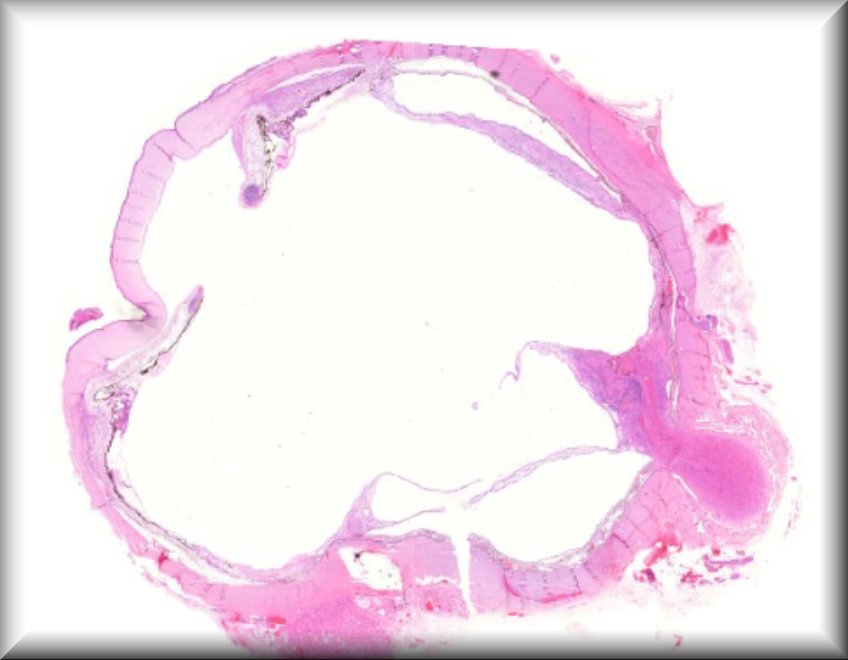

Tero Kivela: Anterior chamber extension of retinoblastoma |